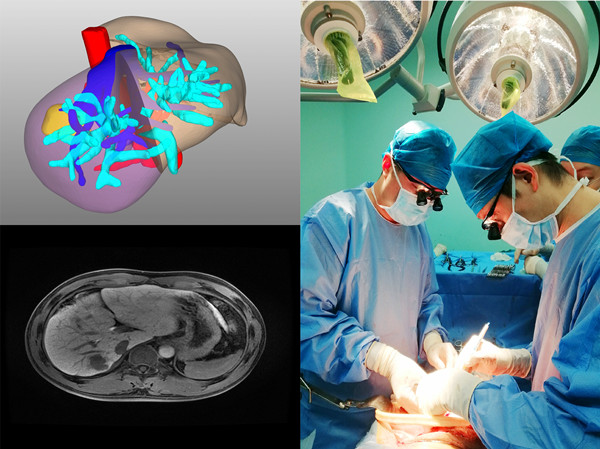

患者1,男,40岁,诊断“原发性肝癌(术后复发)”。术前评估:全身评估及营养评估未见异常;肝功能Child-Pugh-Turcotte分级A级,ICGR15 5.7%;考虑患者系既往解剖性肝段切除后肿瘤复发,故选择解剖性右半肝切除。病灶及可切除性评估:肿瘤位于肝右后叶,毗邻右肝静脉;门静脉无变异(A型),肝动脉无变异,肝静脉无变异;肝内胆管无扩张;患者总肝体积1435.09ml,标准肝体积1314.17mL,右半肝体积523.04mL,左半肝体积占标准肝体积的69.4%(标化余肝率,Rsr),按照《精准肝切除术专家共识(2017版)》要求,患者标化必须余肝率(Rse)为40%